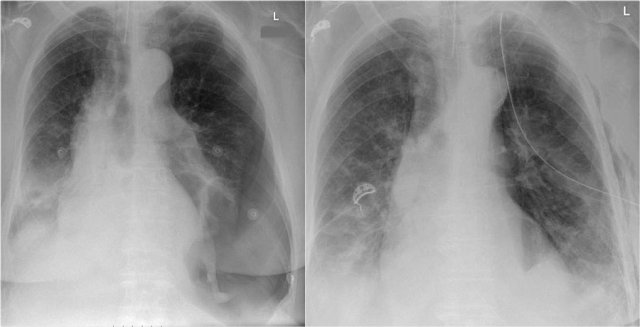

It is extremely important to always compare with old films, as we will demonstrate in this case.

Actually someone said that the most important radiograph is the old film, since it gives you so much information.

For instance a lung mass, which hasn't changed in many years is not a lung cancer.

First study the chest films.

Based on these films, you could make the diagnosis of congestive heart failure, but the findings are subtle.

Continue with the old film...

Scroll back and forth to the old film.

Once you compare the chest film to the old one, things become more obvious and you will be much more confident in your diagnosis of congestive heart failure:

- The size of the heart is slightly increased compared to the old film, but was already large on the old film.

- The pulmonary vessels are slightly increased in diameter indicating increased pulmonary pressure.

- There are maybe some subtle interstitial markings as a result of interstitial edema.

- There is pleural fluid bilaterally. Notice that the infero-posterior border of the lower lobes has changed in position.